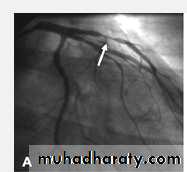

Severe proximal LAD Lesion

Very severe proximal LAD stenosis

Total CX Occlusion